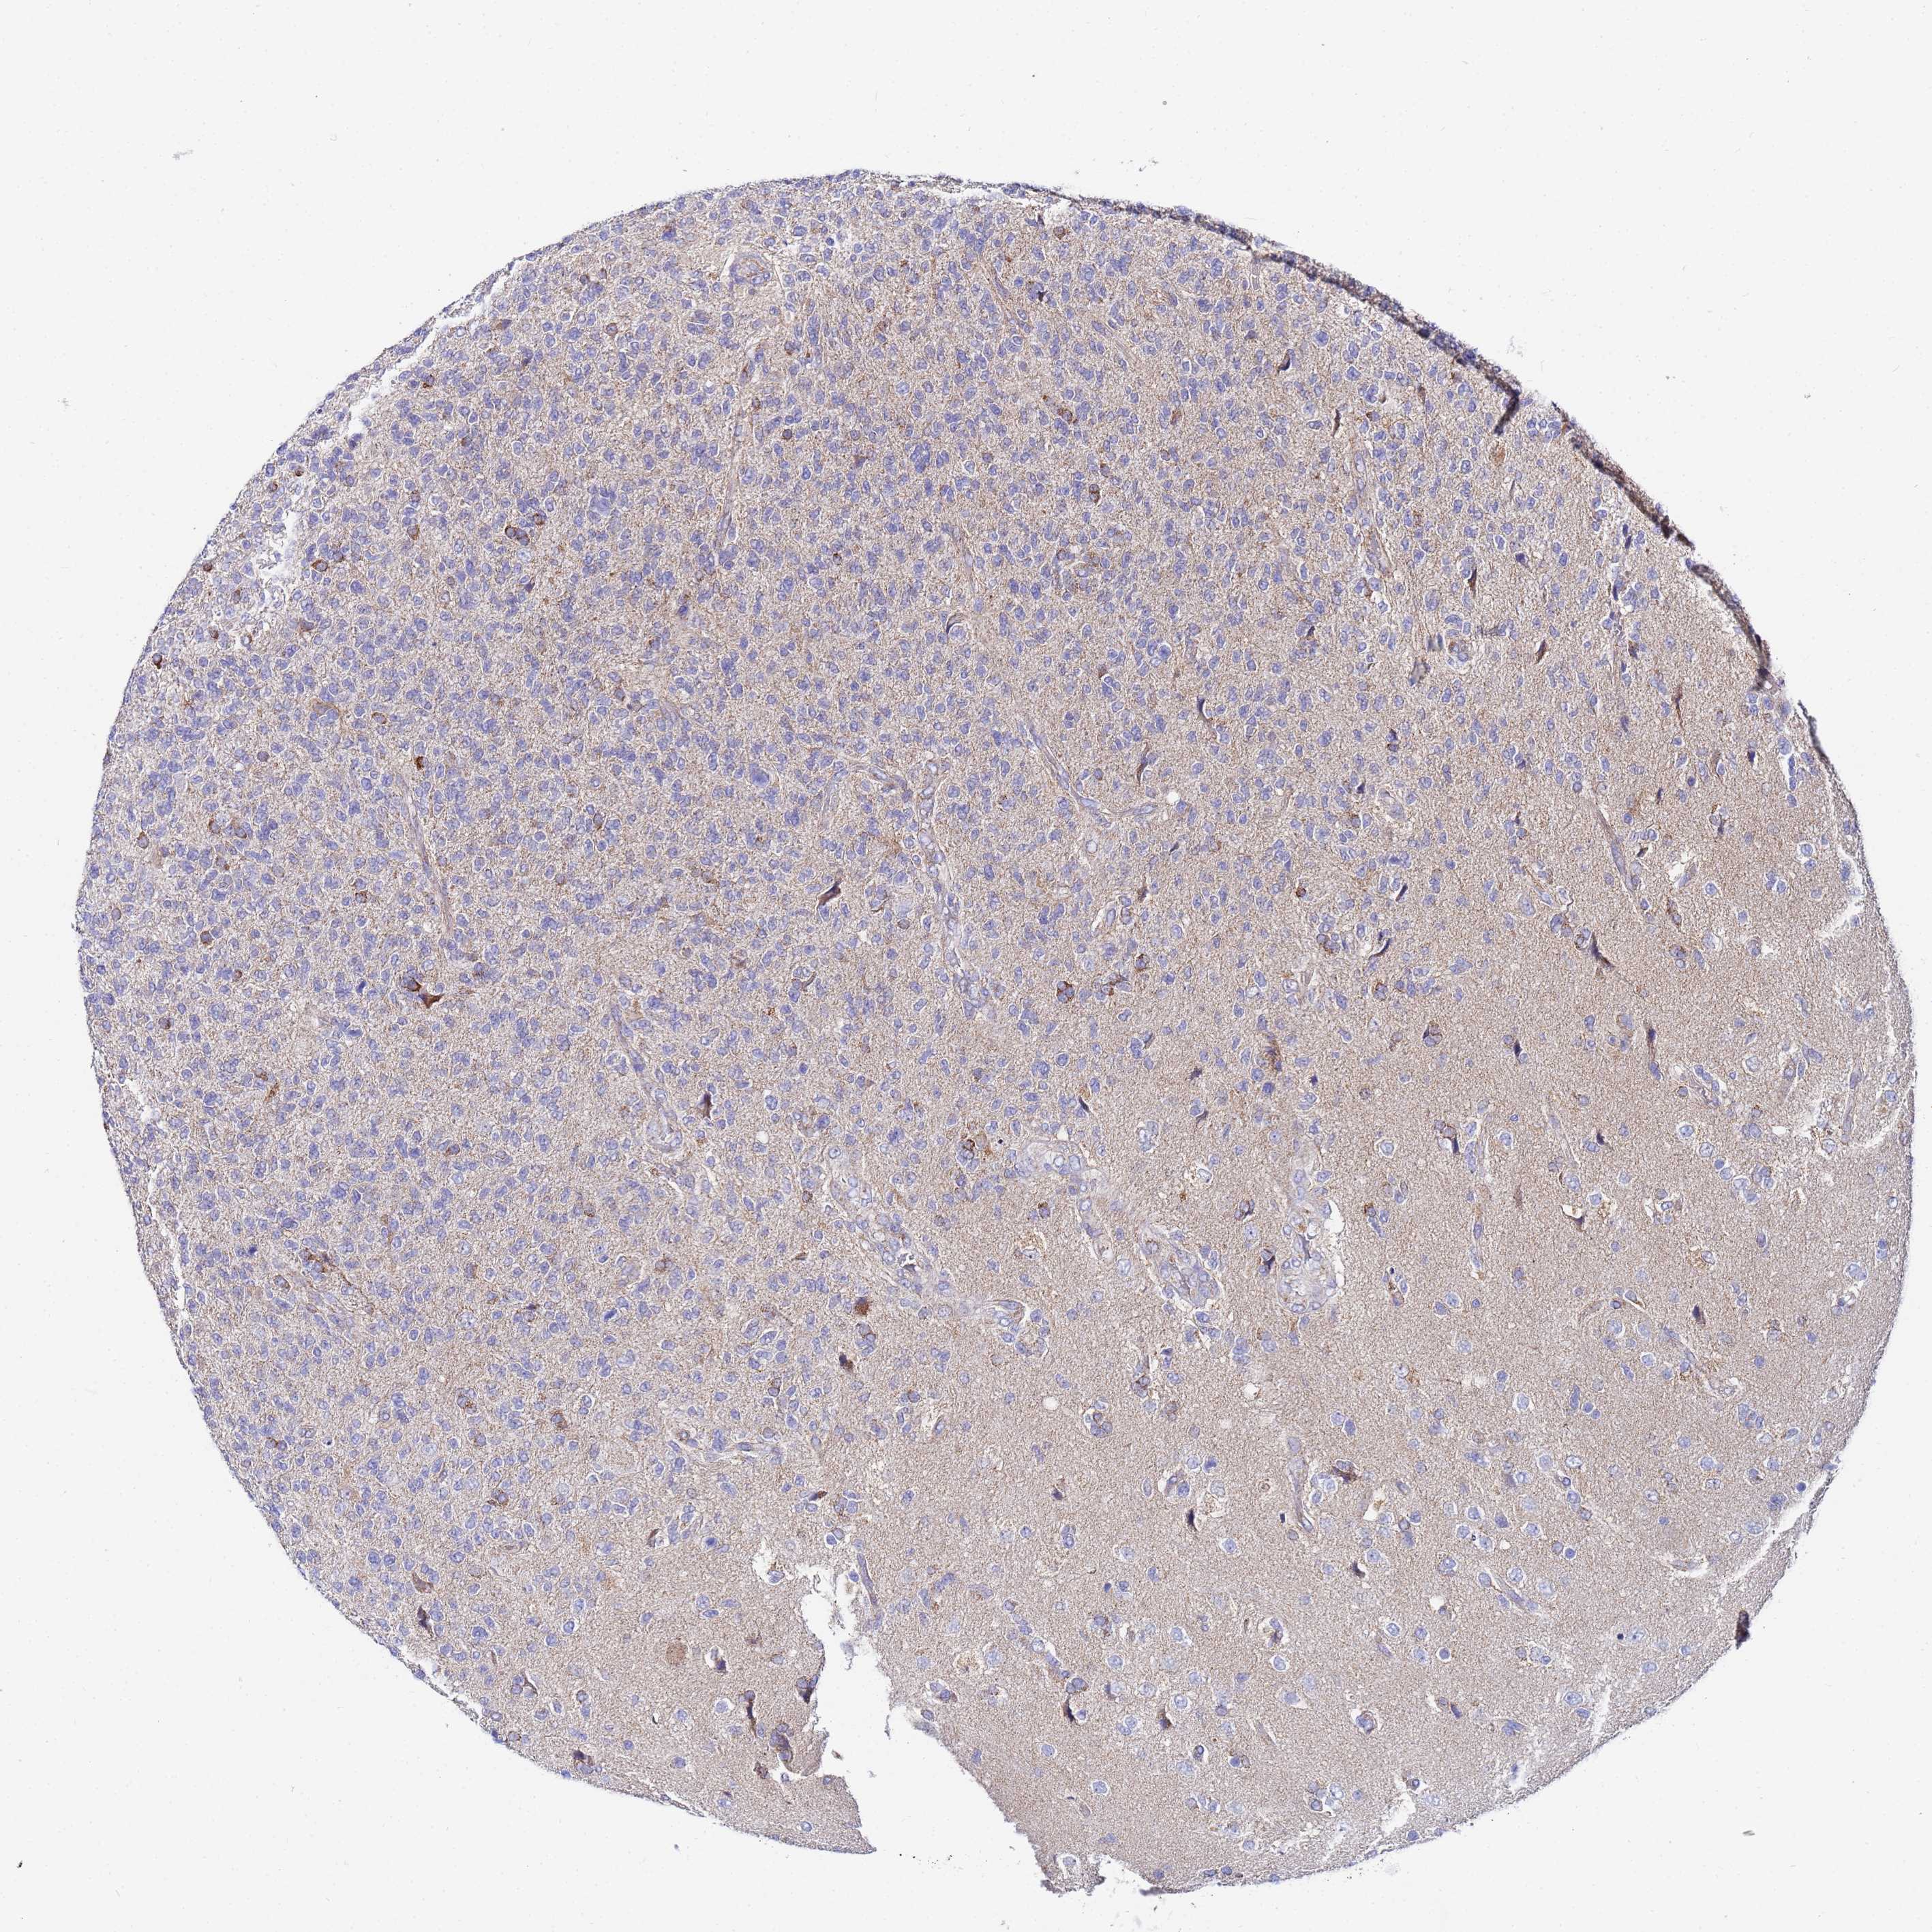

GLIOMA - Protein expressioni

A mouse-over function shows sample information and annotation data. Click on an image to view it in a full screen mode. Samples can be filtered based on level of antibody staining by selecting one or several of the following categories: high, medium, low and not detected. The assay and annotation is described here.

Note that samples used for immunohistochemistry by the Human Protein Atlas do not correspond to samples in the TCGA dataset.

Antibody stainingi

Antibody staining in the annotated cell types in the current human tissue is reported as not detected, low, medium, or high, based on conventional immunohistochemistry profiling in selected tissues. This score is based on the combination of the staining intensity and fraction of stained cells.

Each image is clickable and will lead to virtual microscopy that enables deeper exploration of all samples and also displays staining intensity scores, fraction scores and subcellular localization as well as patient and tissue information for each sample.

Antibody HPA042145

Antibody HPA044987

Antibody CAB045971

Antibody CAB045972

Staining

High

Medium

Low

Not detected

Intensity

Strong

Moderate

Weak

Negative

Quantity

>75%

75%-25%

<25%

None

Location

Nuclear

Cytoplasmic/membranous

Cytoplasmic/membranous,nuclear

Glioma, malignant, Low grade

Glioma, malignant, High grade